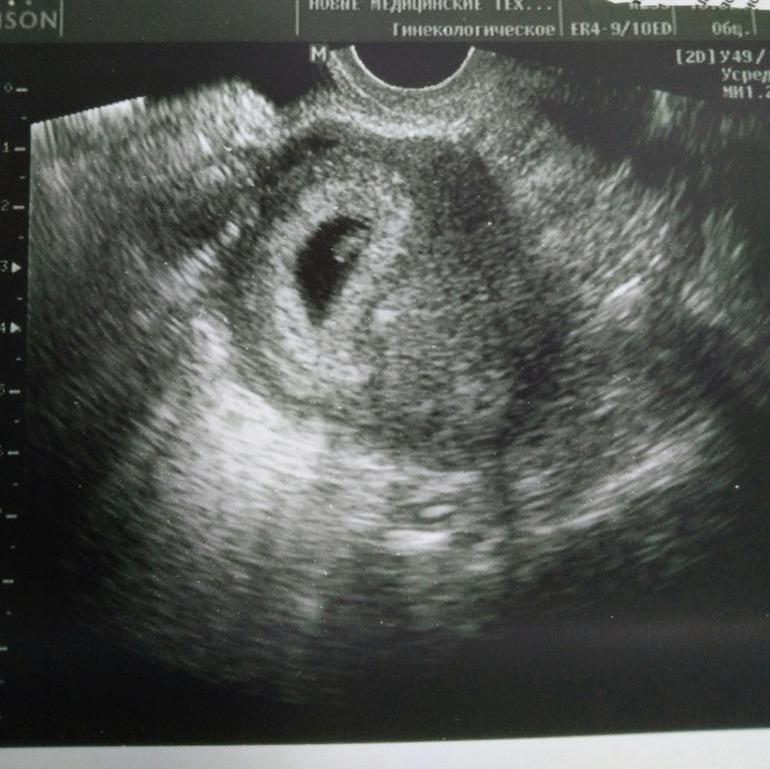

Была на узи. 6нед 4 дня

Была на узи, все там супер, отслойки нет, тонуса нет, малыш живой, сердечко бьется.

Рубец хороший, 4,6 мм. В общем, никаких проблем.